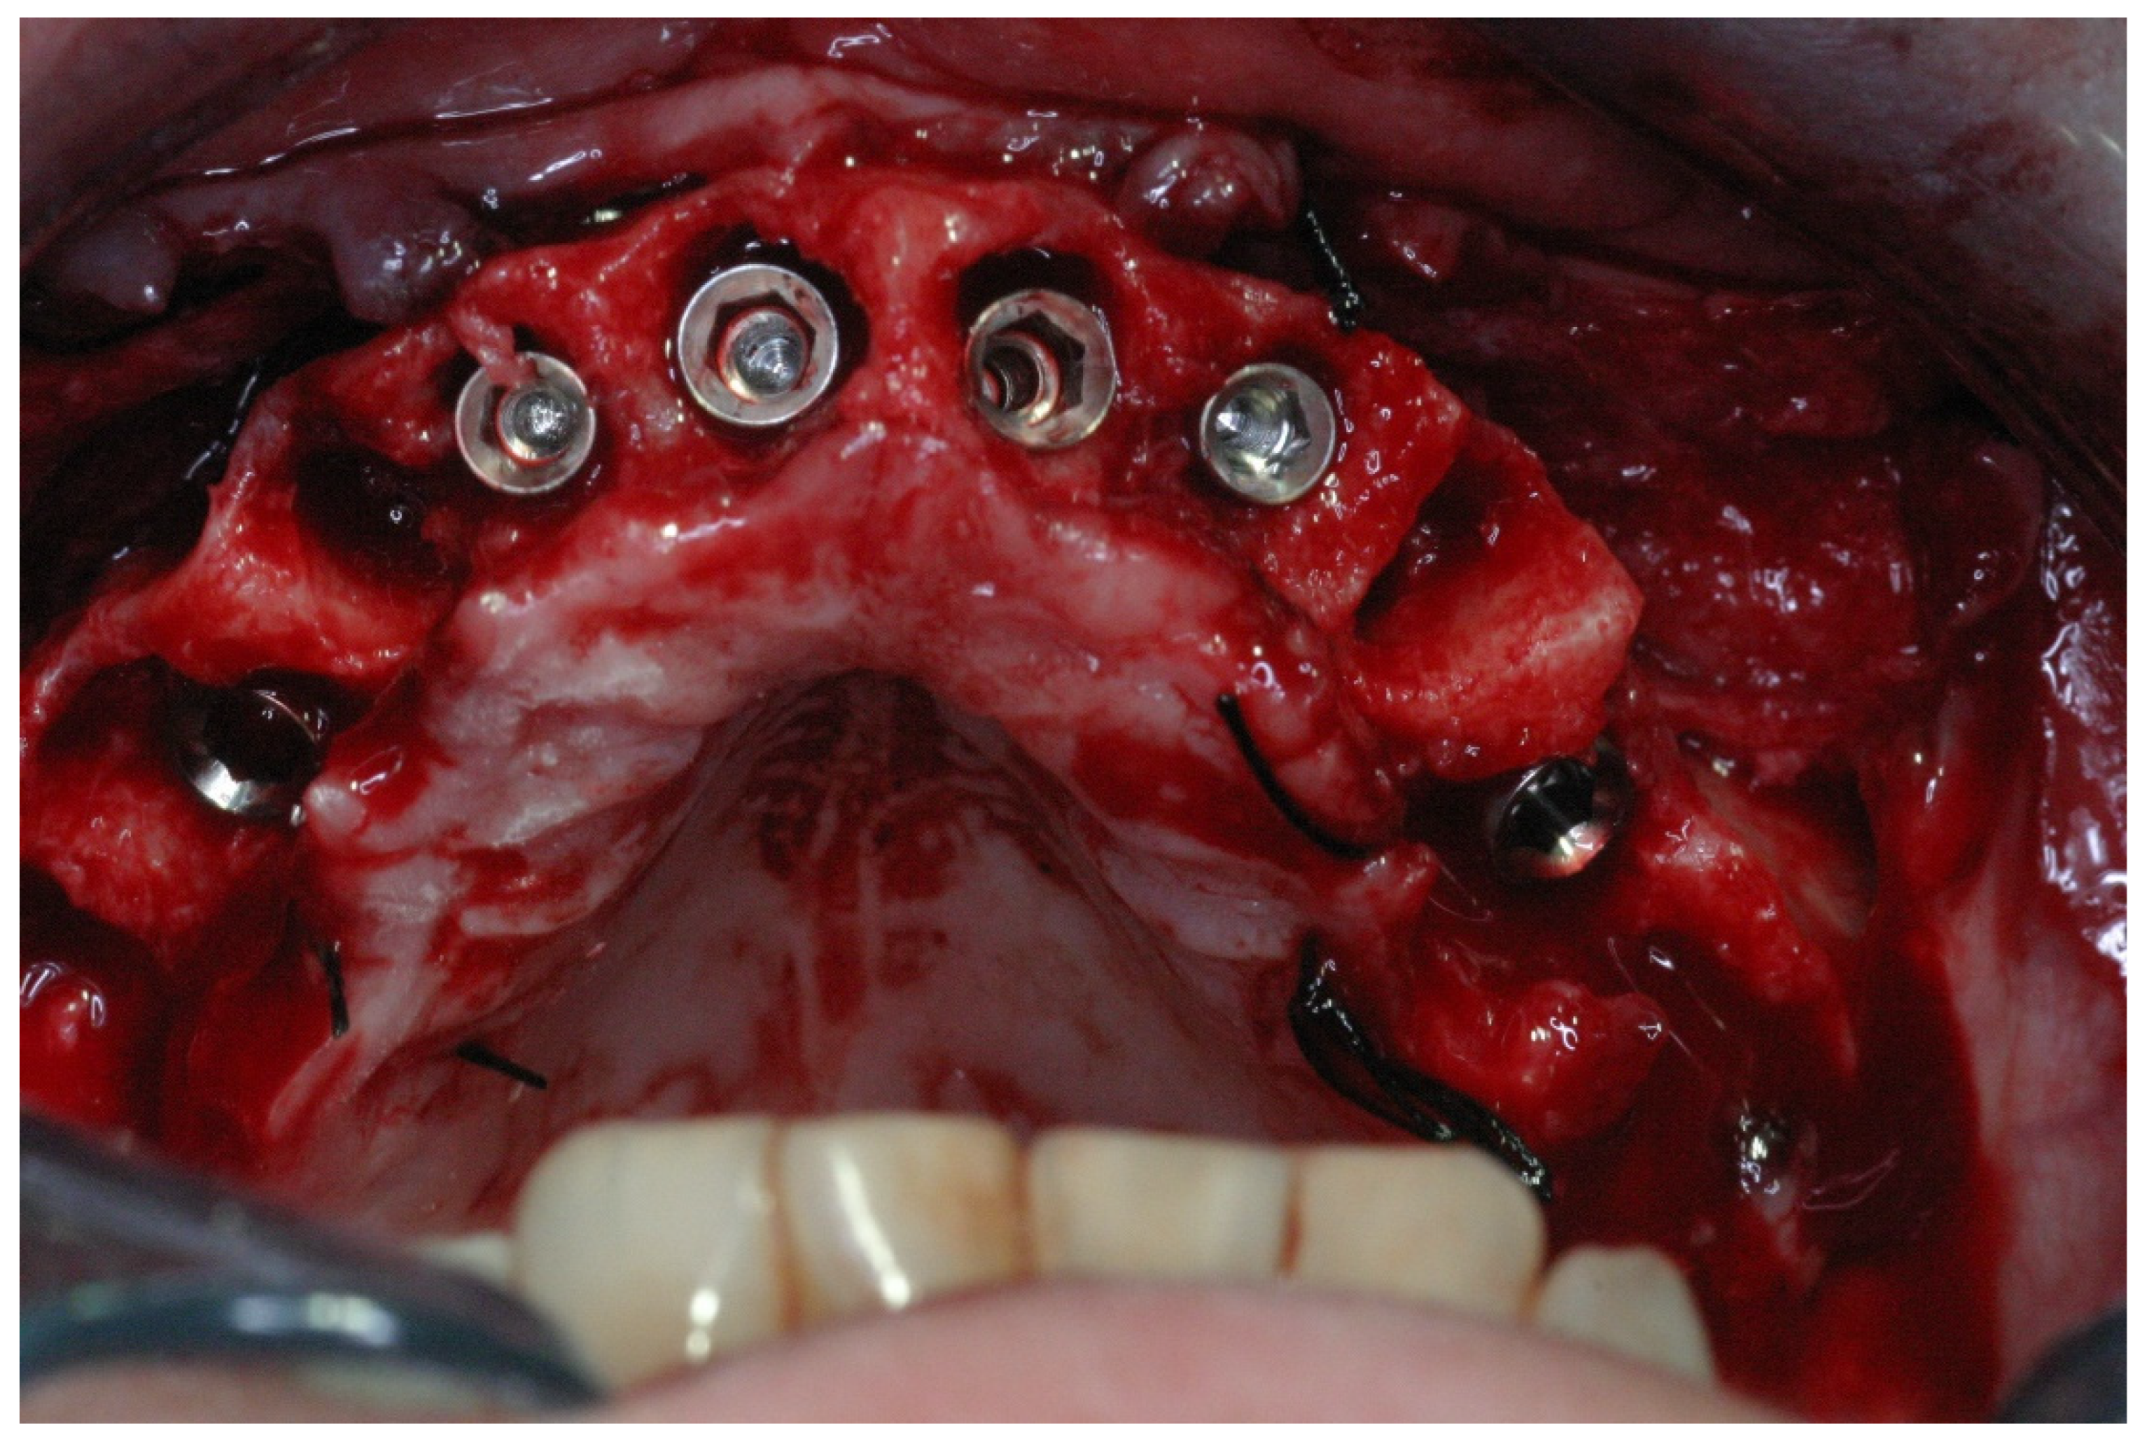

2.2. Surgical Treatment

2.3. Prosthetic Protocol